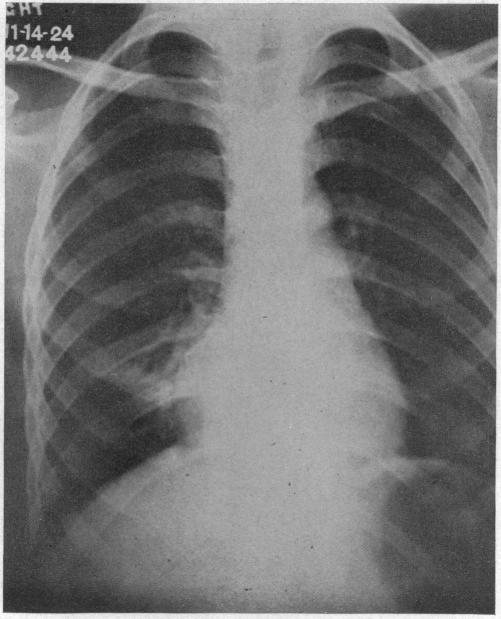

ACUTE MASSIVE COLLAPSE OF THE LUNGS: A DISCUSSION OF ITS MECHANISM AND OF ITS RELATION TO FOREIGN BODIES IN THE BRONCHI AND POST-OPERATIVE COMPLICATIONS.

摘要